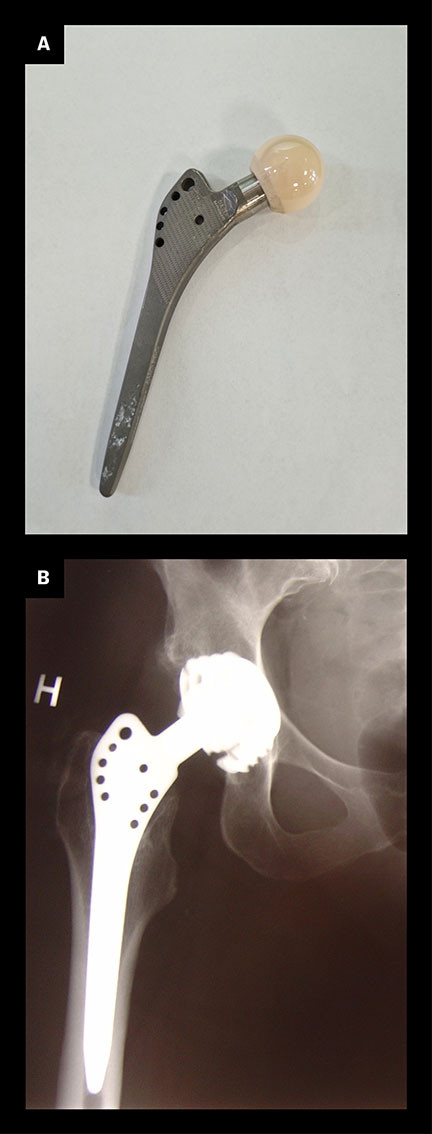

Interest in the orthopaedic use of titanium came somewhat later than in dentistry, but early in the 1980s it became clear that cementless hip prostheses with an alloy of cobalt, chromium and molybdenum (CoCrMo), known in medicine as Vitallium, gave poor bone fixation and weak clinical outcomes (13). These problems led to increased interest in improving cementless prostheses. Greater understanding of the osseointegration of implants resulted in the development of the first cementless titanium hip prosthesis. It was introduced under the name Zweymüller, after the Viennese orthopaedist who started testing it in 1980 (14) (Figure 2). In Norway, titanium femoral prostheses were introduced in 1984 (15). All cementless primary femoral prostheses now inserted in Norway are made of titanium, and the 20-year survival rate of such implants is over 90 % (16).